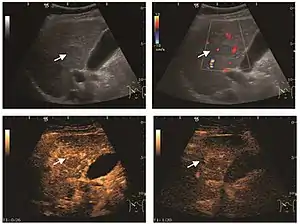

Hemangioma

It is the most common liver tumor with a prevalence of 0.4 – 7.4%. It is generally asymptomatic but also can be associated with pain complaints or cytopenia and/or anemia when it is very bulky. It is unique or paucilocular. It can be associated with other types of benign liver tumors. Characteristic 2D ultrasound appearance is that of a very well defined lesion, with sizes of 2–3 cm or less, showing increased echogenity and, when located in contact with the diaphragm, a "mirror image" phenomenon can be seen. When palpating the liver with the transducer the hemangioma is compressible sending reverberations backwards. Doppler exploration reveals no circulatory signal due to very slow flow speed. CEUS investigation has real diagnosis value due to the typical behavior of progressive CA enhancement of the tumor from the periphery towards the center. The enhancement is slow, during several minutes, depending on the size of hemangioma and on the presence (or absence) of internal thrombosis. During late (sinusoidal) phase, if totally "filled" with CA, hemangioma appears isoechoic to the liver. Deviations from the above described behavior can occur in arterialized hemangiomas or those containing arterio-venous shunts. In these cases, differentiation from a malignant tumor is difficult and requires other imaging procedures, follow up and measurements of the tumor at short time intervals.[4]